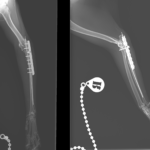

猫ちゃんがお家から居なくなり、探していたところお庭でうずくまって居るところを発見されました。かかりつけの動物病院で両側のモンテジア骨折と診断されました。(原因は落下事故と判明)外科的整復のため当院へ搬送されました。橈骨頭を整復したのち、尺骨にIM pinを刺入、2.0-Locking Plateで固定術を行いました。橈骨頭へ尺骨側からポジションスクリューで固定を併用します。このスクリューは約4週間を目安に抜釘を予定しています。